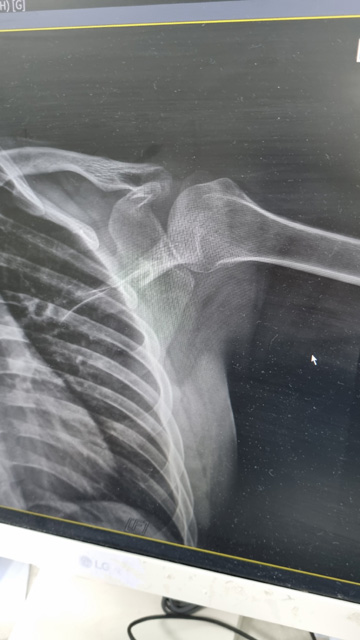

시은 쇄골 골절 2023.3.13

입학하자 말자 고대 여자축구부에 들어가겠다는 포부를 가지고 FC 엘리제 트라이아웃에 참가했던 시은이는 연습 경기에서 태클에 걸려 넘어지면서 왼쪽 쇄골골절을 입었습니다.

왼쪽 쇄골 골절입니다.